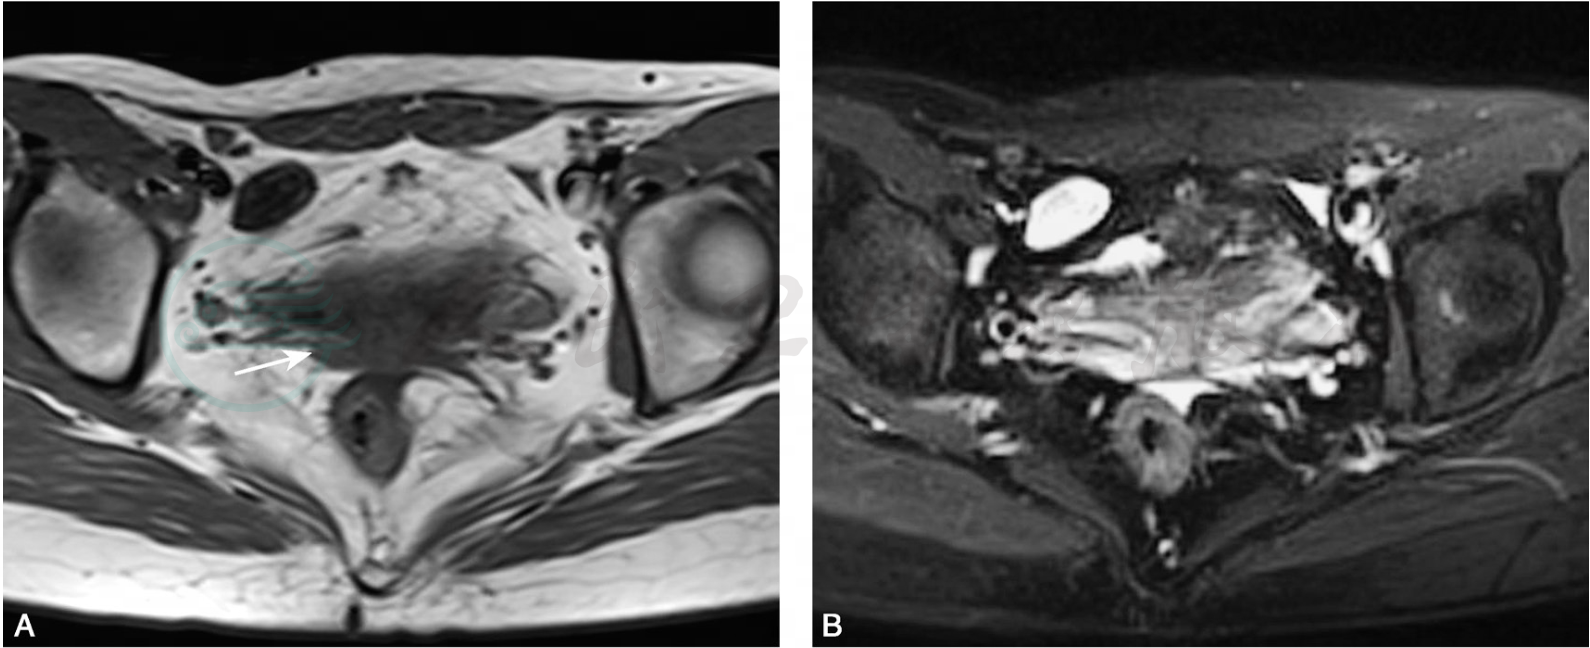

B超、CT或MRI上,在正常子宫位置均无法看到子宫形态及结构,MRI矢状位T2WI显示最佳,有时在直肠膀胱之间可有条索状结缔组织,信号较混杂(图1)。

图1 先天性无子宫

横断位T1WI(A)、横断位及矢状位T2WI脂肪抑制(B,C),膀胱与直肠之间未见正常子宫结构,可见条索状未发育软组织(箭)。冠状位3D-space重建(D)示膀胱上方软组织信号灶,未见正常子宫结构(箭)